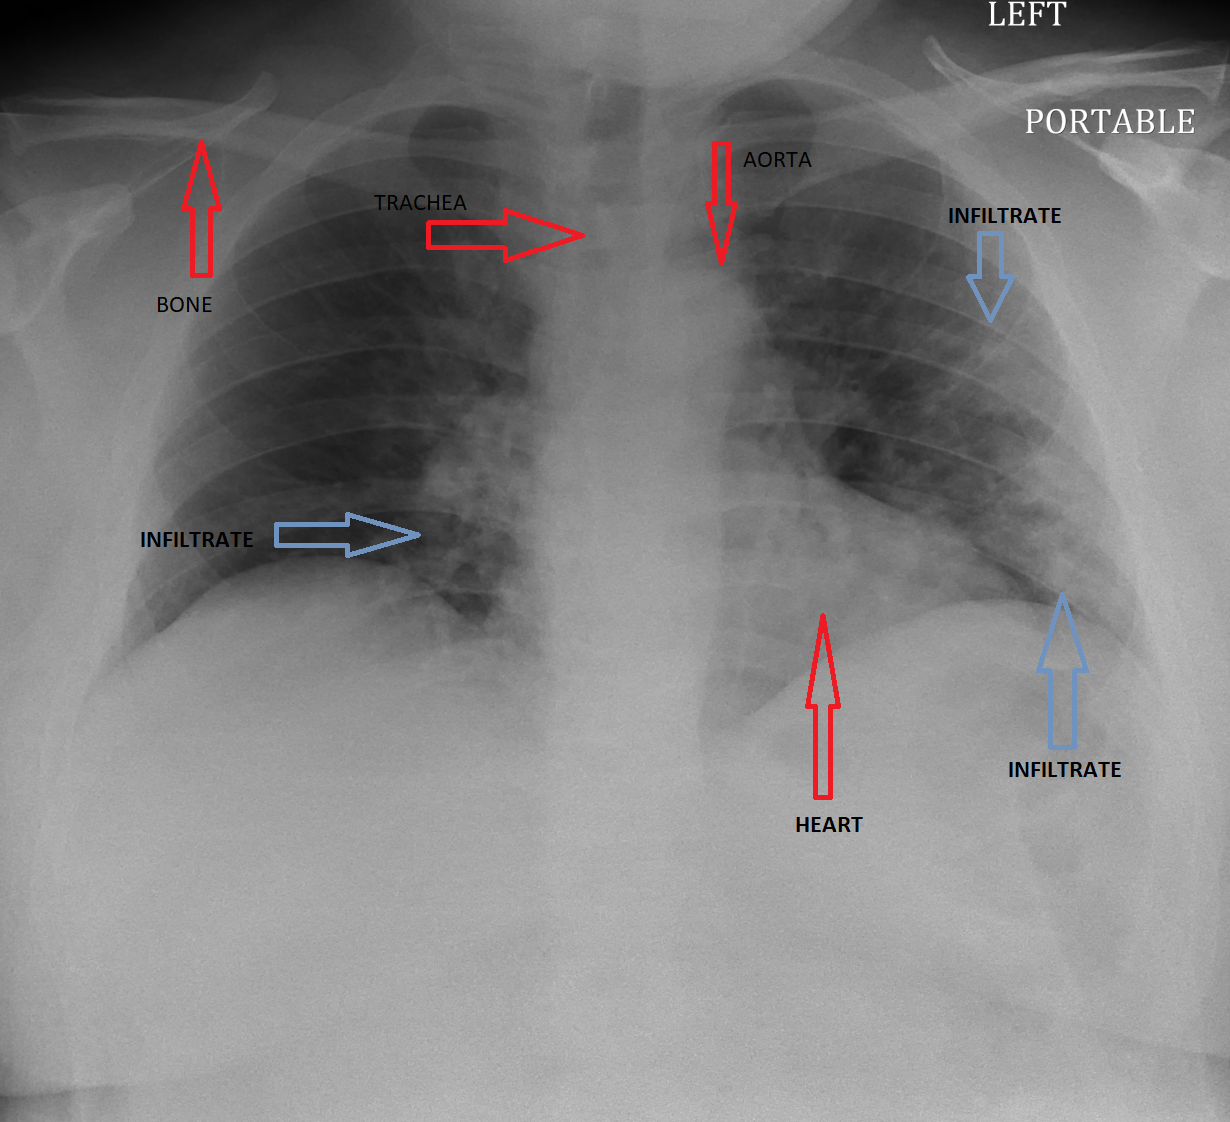

Легкие Ковид19 Фото

Легкие Ковид19 Фото 112 фотографий